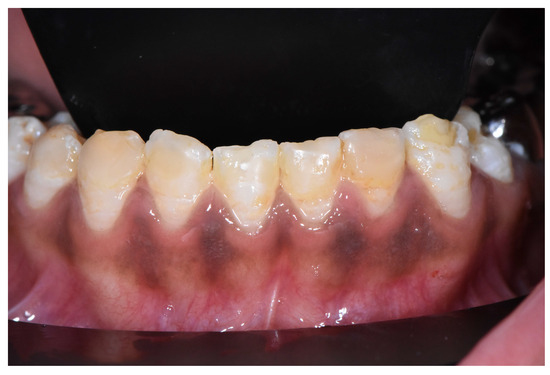

2.2. Clinical Examination

2.9. Anterior Mandibular Teeth Whitening (Fifth Session)